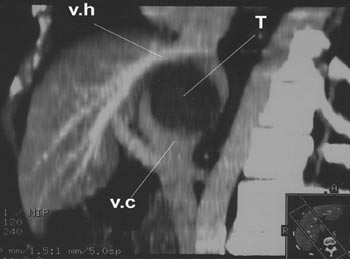

Operasjonen ble utført 30.4. 2001. Etter mobilisering av leveren fikk man god tilgang til neoplasmet, som viste seg å være totalt adherent til v. cava i et område som strakte seg fra levervenenes innmunning i v. cava kranialt til innmunningen av venstre nyrevene kaudalt. Å løsne neoplasmet fra v. cava viste seg ikke å være mulig. Det ble da anlagt ekstrakorporeal veno-venøs bypass til v. brachiocefalica fra høyre v. femoralis og fra v. mesenterica inferior (7), og leveren ble tatt ut sammen med neoplasmet og den retrohepatiske v. cava etter at leverkarene og gallegangen var fripreparert og avsatt. Leveren med tilhørende vev ble straks plassert på et sidebord, hvor den ble lagt i iskjølt saltvannsløsning og perfundert med standard preservasjonsløsning (8). Heller ikke ex situ var det mulig å løse neoplasmet fra v. cava. Hele v. cava med neoplasmet ble derfor fjernet fra leveren (fig 2). V. cava ble så erstattet av en 22 mm goretexprotese, og de tre levervenene ble koblet til denne protesen, som vist i figur 3. Leveren ble deretter brakt tilbake til pasienten hvor vaskulær rekonstruksjon ble gjennomført som ved regulær levertransplantasjon (9). Leveren ble revaskularisert etter at pasienten hadde vært anhepatisk i 4 timer og 43 minutter. Den veno-venøse bypass ble avsluttet og gallegangen ble rekonstruert ved en ende-til-ende-anastomose.